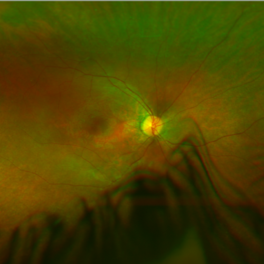

Left eye of a patient with LCA RPE65 showing vascular attenuation with RPE changes.

Condition/keywords: Leber's congenital amaurosis, retinal pigment epithelium, retinal pigment epithelium (RPE) changes, vascular attenuation